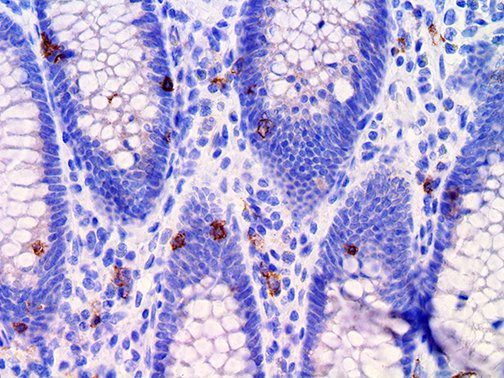

This activation induces inflammatory monocytes to highly express IL-6, starting a localized and then systemic cascade effect that results in hyperproduction of IL-6, which accelerates the inflammatory process. Because IL-6 also increases vascular permeability, excessive levels cause blood vessels to become very leaky. This, along with clotting factors released from vascular endothelial cells, stimulates the coagulation cascade, resulting in microthrombosis (tiny clots), which leads to ischemia and tissue death of the kidney, intestines, heart, liver, brain and extremities.